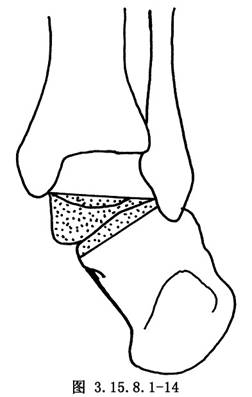

6.5.3 3.截骨矫形

先用骨刀截除跟骰关节和距舟关节,楔形截骨基底在背外侧纠正内翻畸形(图3.15.8.1-8),切除角度等于X线片第2趾和足中线形成的角度(图3.15.8.1-9)。若纠正足外翻畸形,楔形截骨基底可设计在内侧(图3.15.8.1-10),由于距舟关节和跟骰关节在一个平面上,切除角度是一致的(图3.15.8.1-11)。最后切除距下关节,纠正跟骨内收(图3.15.8.1-12),根据X线片胫骨中线和跟骨中线形成的角度,做外侧楔形切除(图3.15.8.1-13)。当骨刀切到对侧时,注意轻缓,尤其纠正外翻时,更要注意防止误伤胫后的血管及神经(图3.15.8.1-14)。将已切除的骨面合拢,如畸形纠正,骨面能紧密对合(图3.15.8.1-15),周围空隙植入切除多余的松质骨。